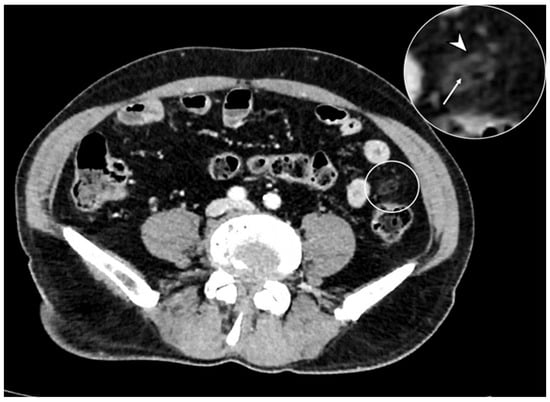

Figure 11. Axial contrast-enhanced CT shows an oval mass with adipose tissue density located on the antimesenteric side (circle), which presents fat inflammation, demonstrated by peripheral hyperdensity (arrowhead in detail) and central thrombosed vein (arrow in detail). These findings are consistent with epiploic appendagitis.

The epiploic appendages are protrusions of fatty tissue located on the antimesenteric side of the colon. In case of torsion or thrombosis of their vascular pedicle, they can manifest ischemia and inflammation and aim for acute diverticulitis with phlegmon [38]. CE-CT shows an oval mass with adipose tissue density located on the antimesenteric side and with peripheral hyperattenuating (hyperattenuating ring sign), expression of inflamed fat, and a central focal area of hyperattenuating (central dot sign), which corresponds to the thrombosed vein within the inflamed appendage (Figure 11) [39]. Compared with acute diverticulitis, the associated diverticular disease is not present in appendagitis without colonic wall thickening.